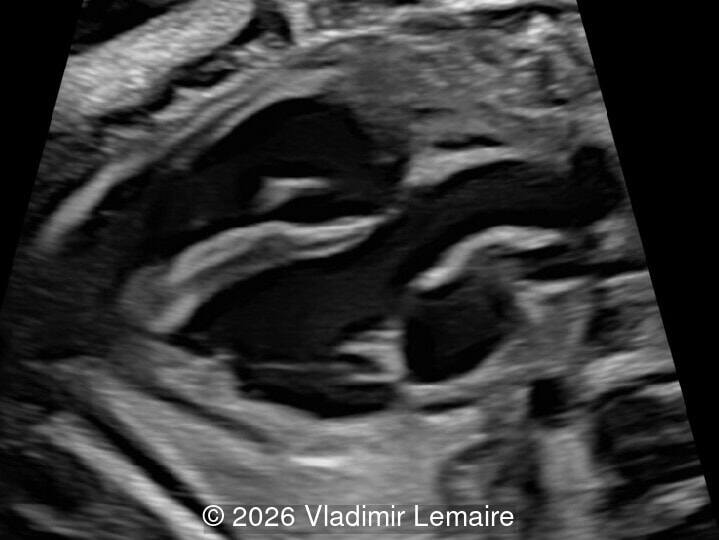

Surface mode rendering looking into the brain of the same fetus with the vein of Galen aneurysmal malformation.

Image 1 Surface mode rendering looking into the brain of the same fetus with the vein of Galen aneurysmal malformation.

We present a case of Vein of Galen Aneurysmal Malformation (VGAM).

Our imaging revealed enlargement of the fetal heart with dilation of the superior vena cava. On further evaluation, we identified an elongated anechoic cystic structure in the midline of the head, without mass effect on the surrounding structures. Color doppler demonstrated an arteriovenous fistula between the deep choroidal arteries and the embryonic median prosencephalic vein of Markowski. The vein of Galen aneurysmal malformation was likely the contributing factor to the cardiac enlargement. Cardiac function was, however, preserved and hydrops not present. Additional images are shown below.